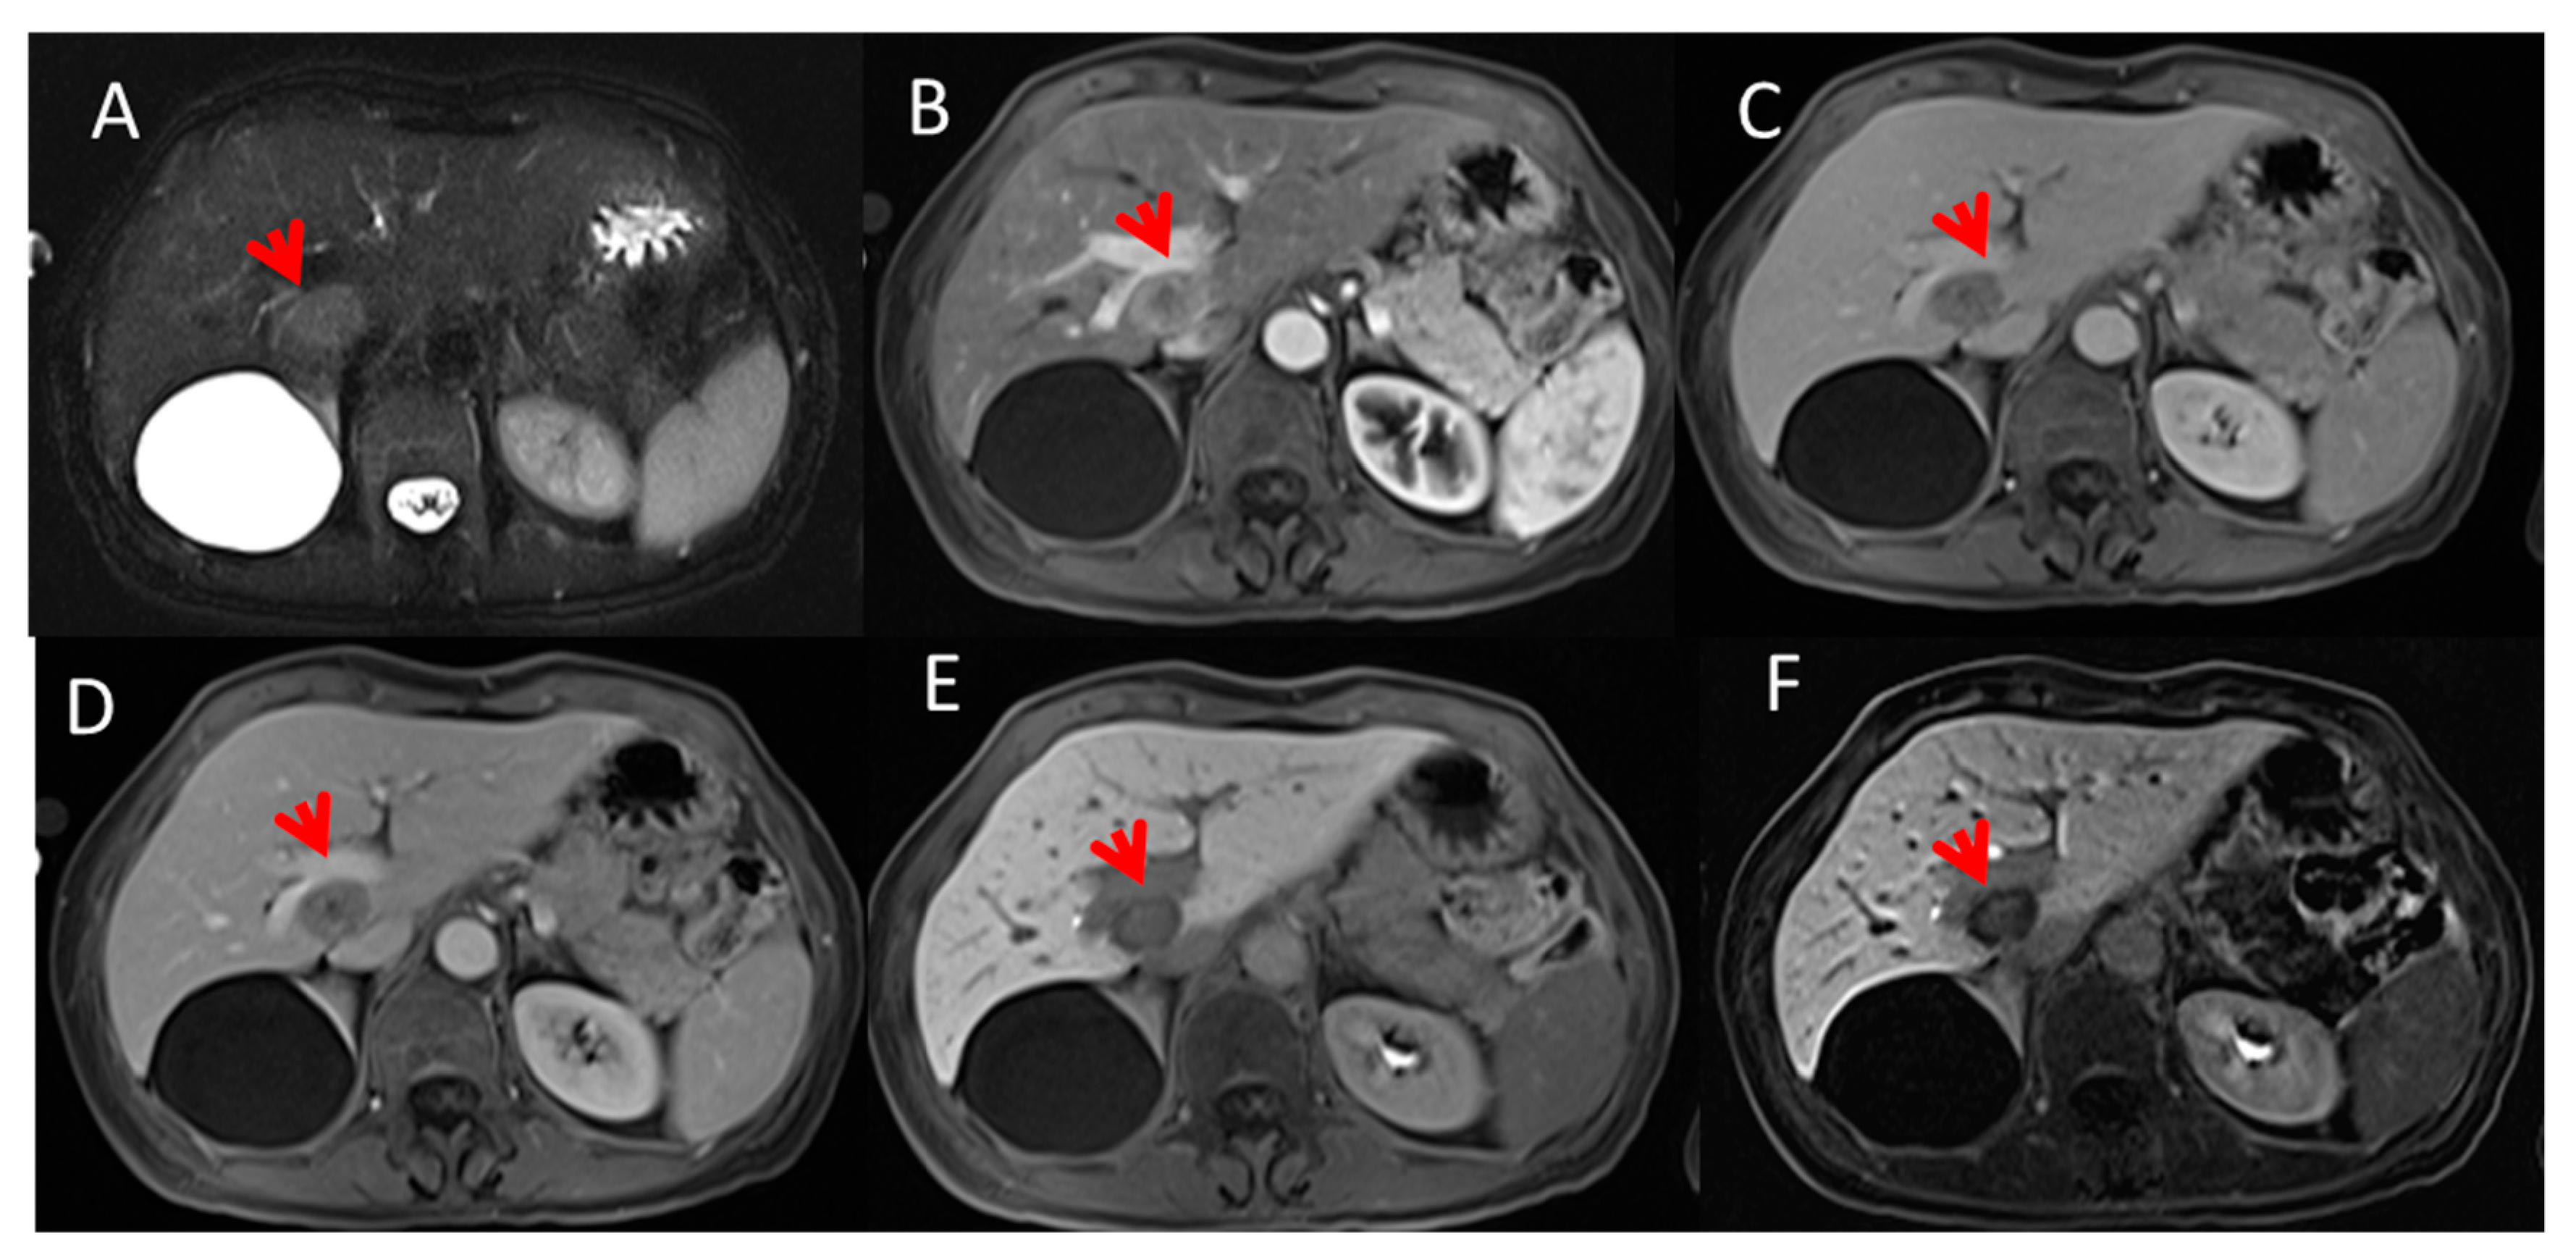

2.2. MR Imaging Protocol

2.3.1. Texture Features